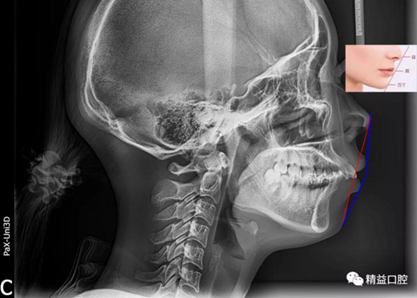

矯正前頭顱側(cè)位片

嘴唇突度非常明顯,后期經(jīng)過測量,發(fā)現(xiàn)是典型的安氏II類加骨性II類,齙牙前突。